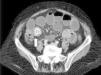

Upon admission to the Emergency Department, the symptoms the patients complained of were vomiting (14; 100%), colicky abdominal pain (12; 85.7%), and absence of bowel transit (5; 35.7%) of 2-day progression (1; 4). After the initial evaluation, blood tests were ordered and their results were: hemoglobin 14.8g/dl (13.2; 16.1), hematocrit 44% (38.7; 48.1), leukocytes 12100/mm3 (8,800; 18,600), neutrophils 86.5% (80; 89), urea 79mg/dl (58; 96), and creatinine 1.3mg/dl (1; 2). Diagnosis was confirmed by abdominal x-ray alone in 4 cases (28.6%) and abdominopelvic computed tomography scan was required in 10 cases (71.4%). Figure 1 shows the example of a case in which diagnosis was established through computed abdominopelvic tomography.